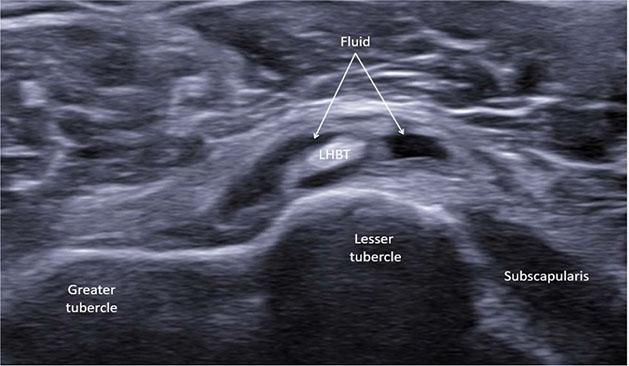

Residual echogenic fibers within the long head of the biceps tendon (LHBT) with surrounding fluid and degenerative changes